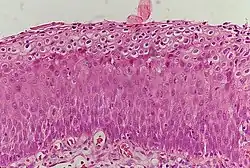

_normal_squamous_epithelium.jpg)

Historically, abnormal changes of cervical epithelial cells were described as mild, moderate, or severe epithelial dysplasia. In 1988 the National Cancer Institute developed "The Bethesda System for Reporting Cervical/Vaginal Cytologic Diagnoses".[12] This system provides a uniform way to describe abnormal epithelial cells and determine specimen quality, thus providing clear guidance for clinical management. These abnormalities were classified as squamous or glandular and then further classified by the stage of dysplasia: atypical cells, mild, moderate, severe, and carcinoma.[13]